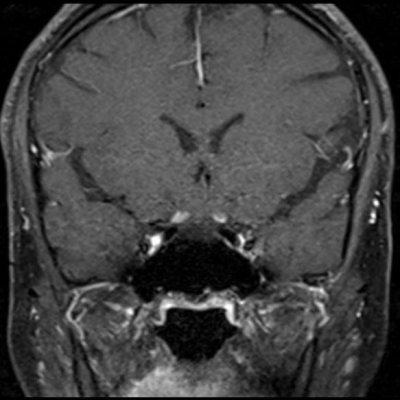

- (B) Orbita MRG’de aksiyel yağ baskılı T1A’da optik sinir prekiazmatik segmenti (oklar) gösterilmiş olup sırası ile aksiyel ve koronal post-kontrast yağ baskılı T1A görüntülerde bilateral optik sinir prekiazmatik segmentte kontrast tutulumu dikkati çekmektedir (oklar ve daire).